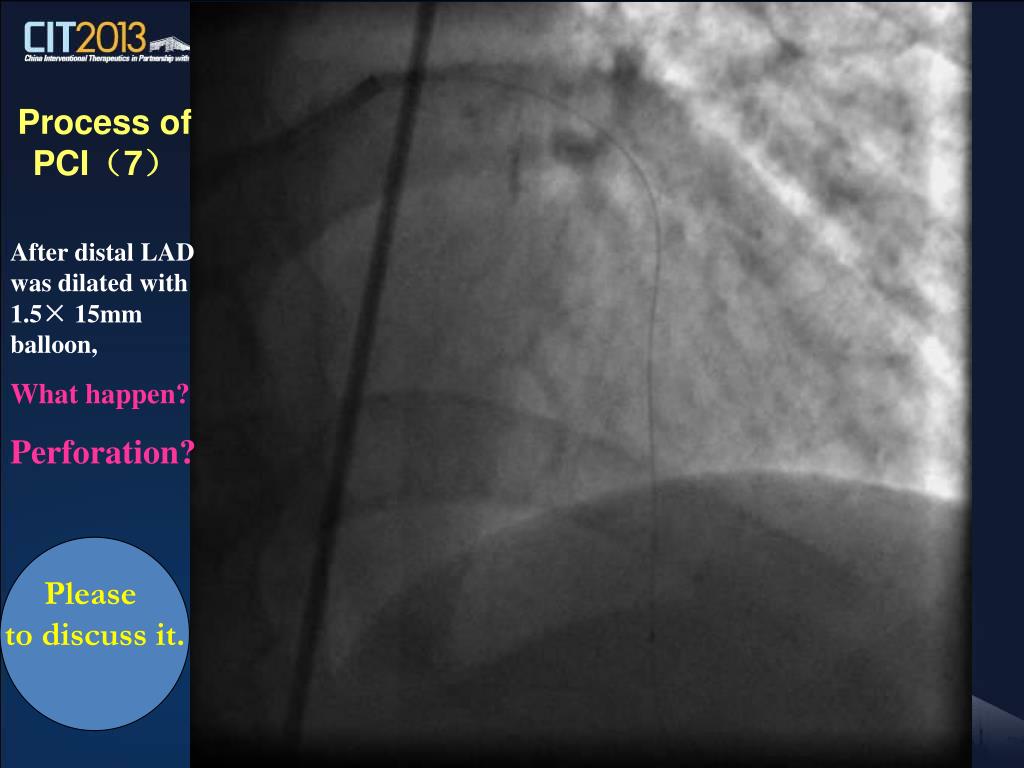

21. Process of PCI(6) Distal LAD was dilated with 1.5× 15mm balloon

22. Process of PCI(7) After distal LAD was dilated with 1.5× 15mm balloon, What happen? Perforation? Please to discuss it.